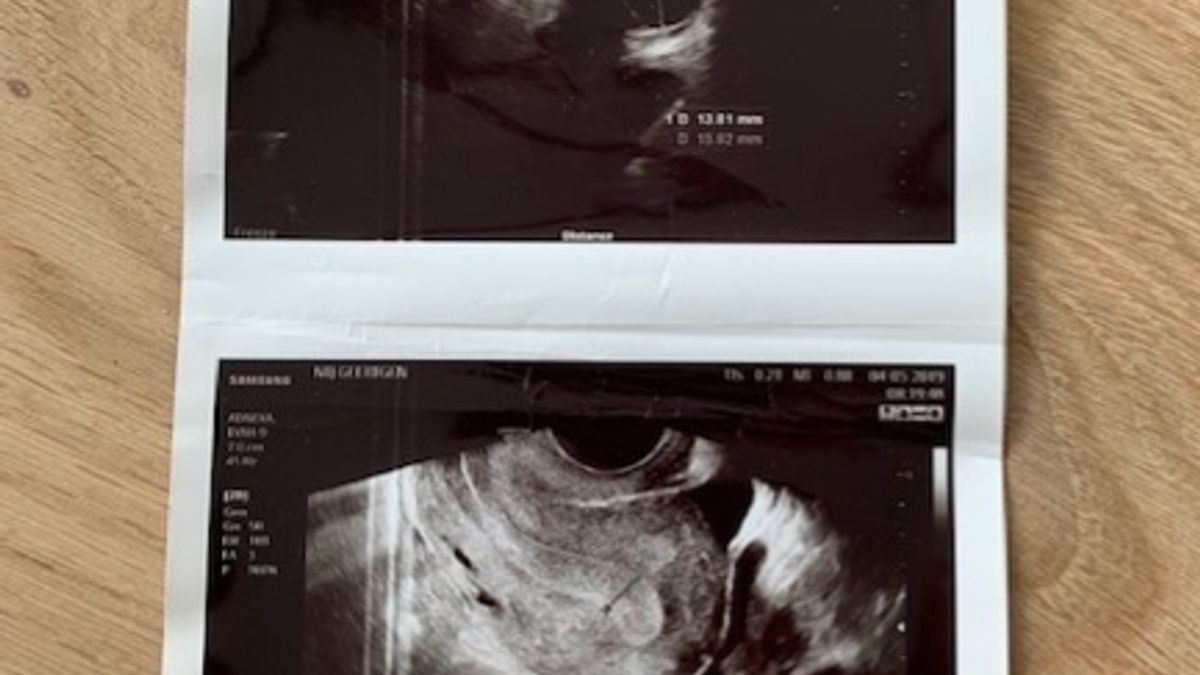

Nadat ik de kuur Provera had genomen, ben ik op de derde dag van mijn menstruatie begonnen met de kuur Clomid. Dit hield in dat ik vijf ochtenden één pilletje in moest nemen. Prima te doen, daarnaast had ik ook geen last van bijwerkingen. Enorm fijn, want ik hoorde via mijn insta-lotgenoten de meest gekke verhalen over de bijwerkingen van Clomid. Eindelijk leek iets ons een keer mee te zitten en ik fietste er zo doorheen, wat fijn! Ik had geen bijwerkingen en daarnaast waren er bij de eerste echo al meerdere groeiende follikels te zien. Ik kreeg zelfs, voor de allereerste keer in mijn hele fertiliteits-carrière, een paar echo foto’s van mijn eigen follikels mee naar huis. Fijn om iets tastbaars te hebben! Je doet er niet veel mee, maar toch.

Bij de tweede controle was er één follikel mooi doorgegroeid. Enorm fijn, aangezien ik normaliter te enthousiast reageer op hormonen en mijn lijf teveel follikels gaat aanmaken. Dit keer was het er gelukkig dus maar één die doorgegroeid was! Dit moest ons gouden ei wel worden. We kregen allebei hoop en de arts was ook enthousiast. De follikel was 14 millimeter, dus moest nog even een aantal dagen doorgroeien. Er werd dus nogmaals een echo ingepland, daarbij kreeg ik het advies om ovulatietesten te doen, om goed in de gaten te houden of mijn lijf uit zichzelf een eisprong in gang zou zetten.